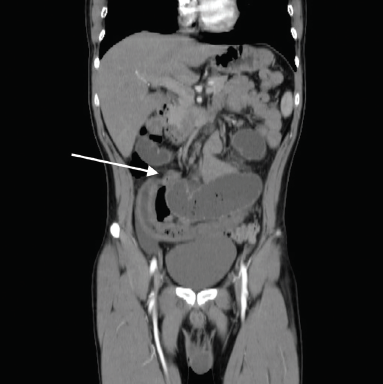

Paciente del sexo masculino, de 26 años de edad, sin antecedentes personales patológicos relevantes, que se presentó al servicio de urgencias con un cuadro de 24 horas de evolución, caracterizado por dolor abdominal en mesogastrio, tipo cólico, sin irradiaciones, EVA 10/10, acompañado de náusea y vómito, así como disminución de evacuaciones. A la exploración física dirigida, peristalsis presente, abdomen blando y depresible, doloroso a la palpación media y profunda en mesogastrio y fosa iliaca derecha. Se realizó tomografía de abdomen con contraste parenteral, en la cual se identificó escaso líquido libre en corredera parietocólica y fosa iliaca derecha, engrosamiento concéntrico de íleon de forma segmentaria, zona de transición con marcada dilatación de asas de íleon terminal (proximal al sitio de transición) (figura 1). Se inició manejo conservador con reposo digestivo con sonda nasogástrica a derivación, reposición hidroelectrolítica y antibioticoterapia, sin mostrar mejoría del cuadro clínico, por lo cual se decidió manejo quirúrgico, se realizó laparotomía exploradora y se reportaron los siguientes hallazgos; divertículo de Meckel con banda mesodiverticular que condiciona hernia interna comprometiendo asa de íleon distal de aproximadamente 25 cm (figuras 2 y 3). Se procedió a liberar asa sin lograr reversión de la isquemia intestinal y viabilidad, por lo que se realizó resección de 30 cm de íleon distal incluyendo el divertículo de Meckel, con posterior entero-entero anastomosis término-terminal, con colocación de drenaje abierto. Con adecuada evolución postquirúrgica, tolerancia a la vía oral, evacuaciones presentes, sin datos de fuga anastomótica, por lo que se decidió su egreso a domicilio al séptimo día postquirúrgico.

Figura 1 En la topografía de íleon terminal, se identifica zona de transición con estructura heterogénea hiperdensa e hipodensa sugestiva de presencia de gas en su interior, y asa proximal dilatada de hasta 7 cm de diámetro.